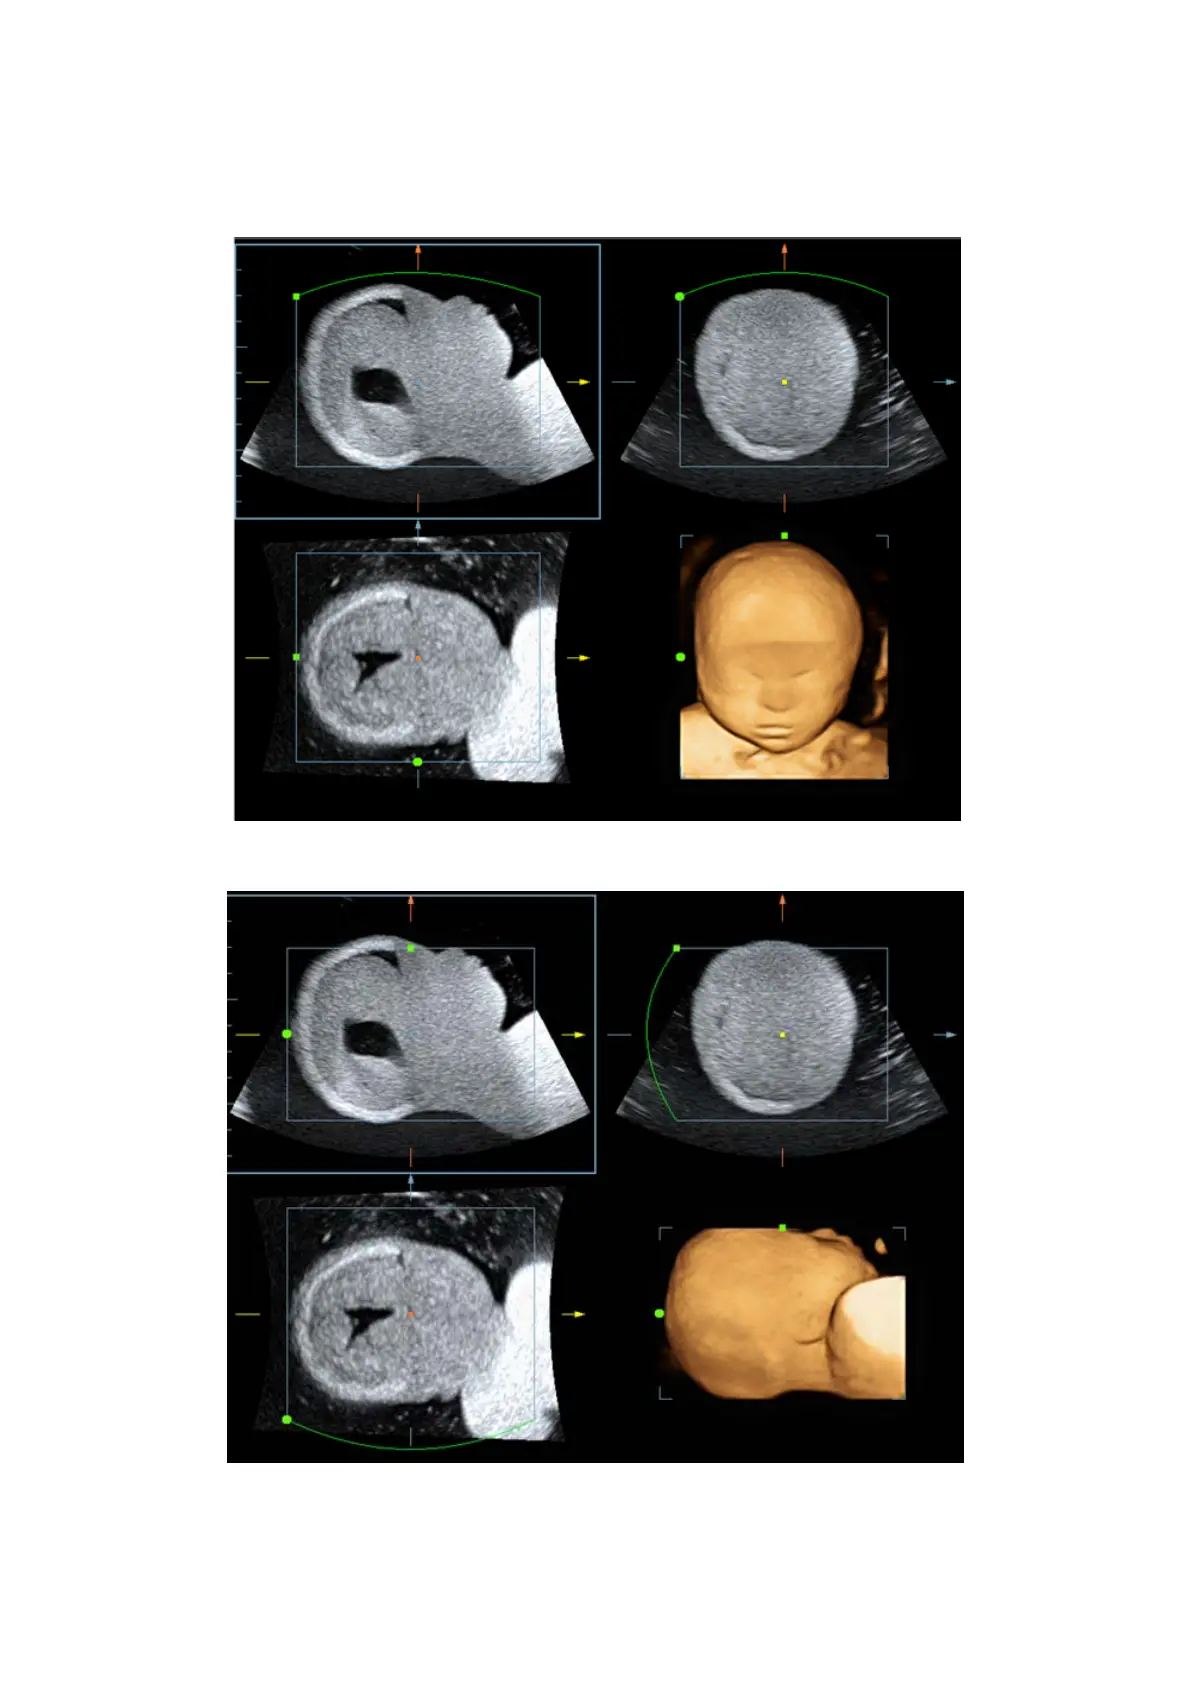

In the following image, the current active plane is MPR A. After performing Sync on

Figure A, you can see the same fetal face profile in VR.

Figure A

Figure B